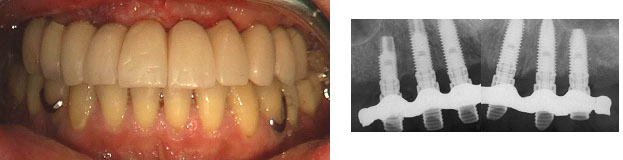

Con questa nuova metodica si costruisce al computer una mascherina chirurgica che ci guida nell'inserimento degli impianti e si esegue un intervento minimamente invasivo senza tagliare la gengiva con il bisturi, senza scollarla e senza applicare punti di sutura. Si eseguono semplicemente 4-6 piccole perforazioni circolari attraverso le quali si inseriscono gli impianti sui quali viene immediatamente applicata una protesi fissa.

Nella fase di pianificazione gli impianti vengono posizionati al computer tenendo conto dell' osso disponibile e, prerogativa esclusiva di questa procedura, del disegno della futura protesi. Il computer realizza quindi la guida che verrà utilizzata dal laboratorio specializzato per realizzare la protesi. La stessa guida permetterà al dentista di posizionare gli impianti con assoluta precisione, senza dover incidere la gengiva, ma praticando esclusivamente dei piccoli fori. Al termine dell' intervento il dentista può applicare la protesi precostruita.

- applicazione immediata di una protesi fissa: il paziente riceve la protesi funzionante appena terminata la fase di inserimento degli impianti e può ritornare alla sua normale vita di relazione dopo poche ore.